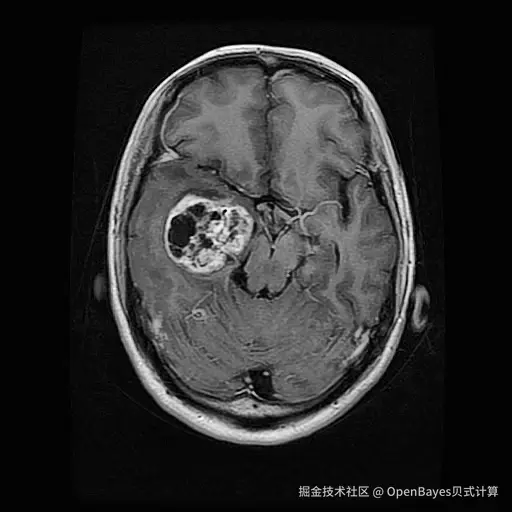

1. Brain Tumor 脑肿瘤数据集

Brain Tumor 数据集是一个脑肿瘤 MRI 分割与分类数据集,旨在为脑肿瘤的医学影像分析提供高质量数据支撑,适用于脑肿瘤分割和分类任务。数据包含约 5,000 张 MRI 切片。